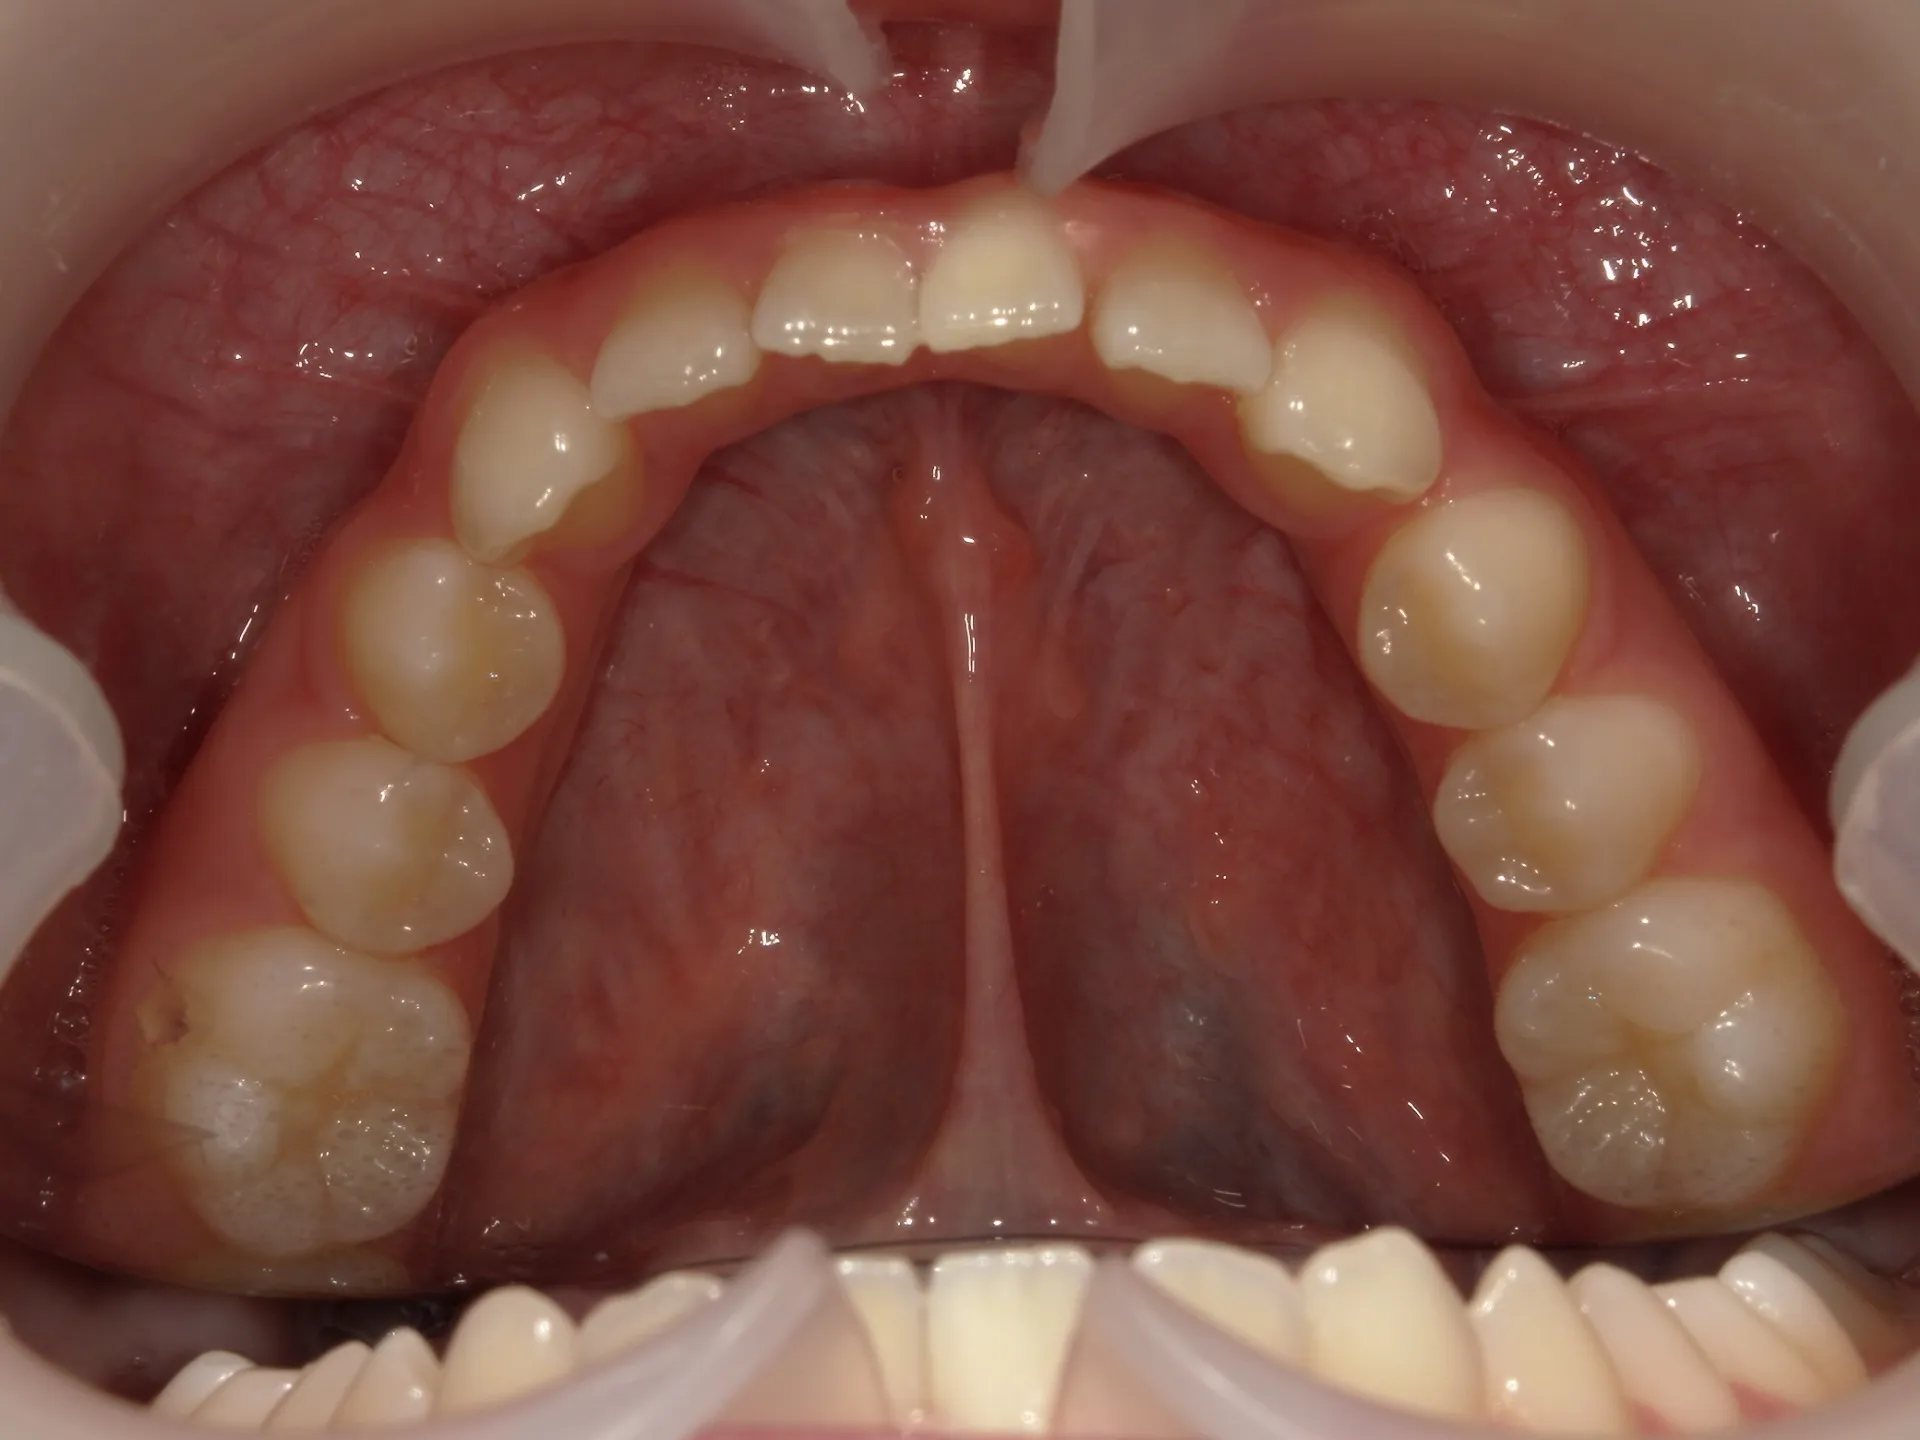

開咬治療前

正面観

まず開咬とは、文字通り開いている咬み合わせのことをさします。

分かりにくい方もいるかもしれませんのでもう少し説明すると、今回お見せしている写真では前歯部開咬と呼ばれる開咬です。

臼歯(奥歯)は噛んでいるのに前歯が咬みあわないで開いているという状態のことを前歯部開咬と言います。

さて、治療前の正面観は先ほど述べた通り、前歯部開咬で奥にある舌が見えているのが分かります。